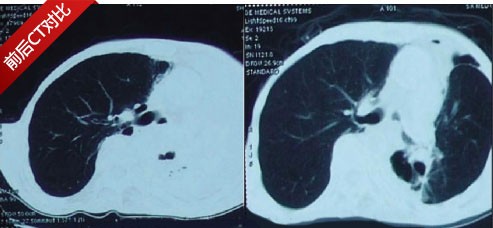

刚开始的时候宋思雅并不十分信任这项技术,但是从电视报道中看到该技术不但精准杀灭癌细胞还没有任何痛苦,宋思雅还是决定试一试,在经两个疗程后,宋思雅明显感觉身上有劲儿了,咳嗽症状消失,复查结果没有发现任何新发转移病灶,这令她信心倍增,自己要求进行下一疗程治疗。